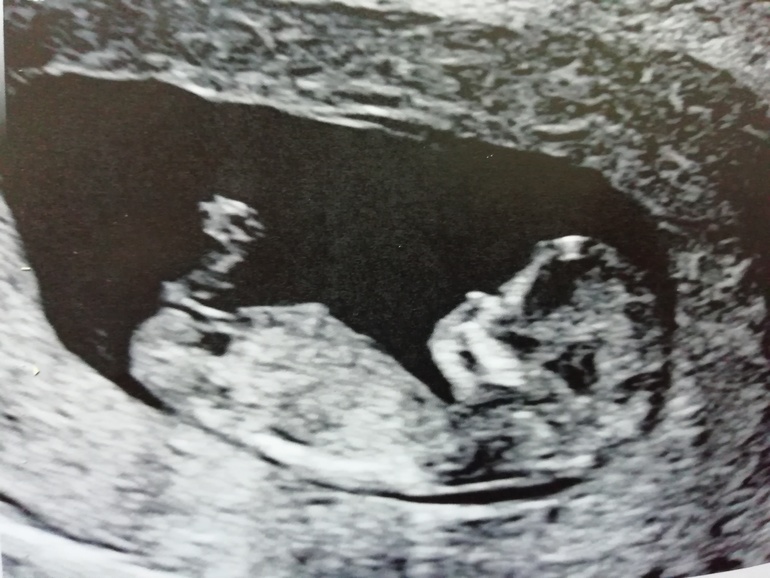

Вопросы про УЗИ, обследования и анализы: что, где, как, когда?Ура-ура, сказали, чудесный здоровый малыш) ктр - 57.8, по М - 12+1 срок. По УЗИ - 12+2.чсс - 160.носик есть), воротниковая зона - 1 мм, сердечко в норме, по 5 пальчиков на ручках и ножках. С полом непонятно пока, сначала показалось больше похоже на девочку, потом - на мальчика. Так что продолжаем ждать результаты НИПТа. Человечек уже!